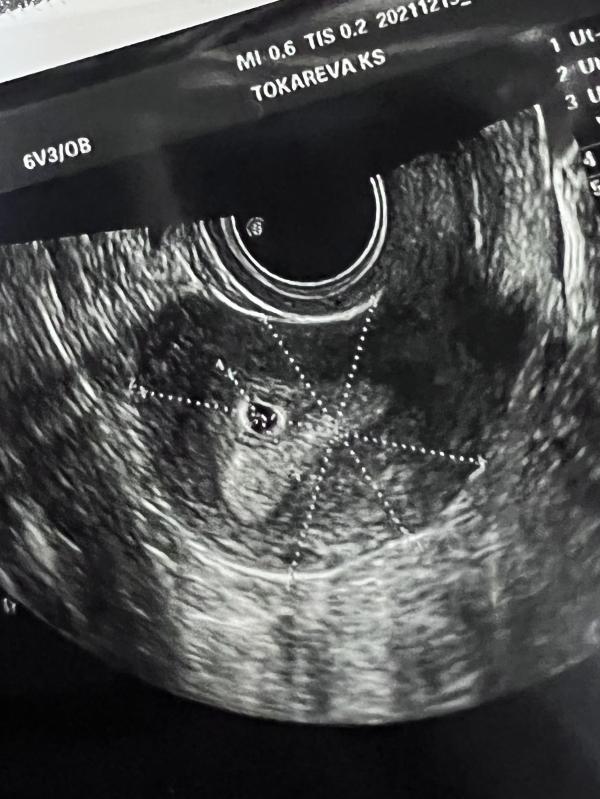

Сходила на узи сегодня! Все отлично, фух. Я прям выдохнула😂 муж до сих пор не знает, жду очень 31 декабря уже! Сказали что из за поздней ов. Примерно около 4 недель срок. Может чуть больше. Сказали через 2 недели придти. А так все хорошо, красивенько по словам врача моей😀 можно спать спокойно